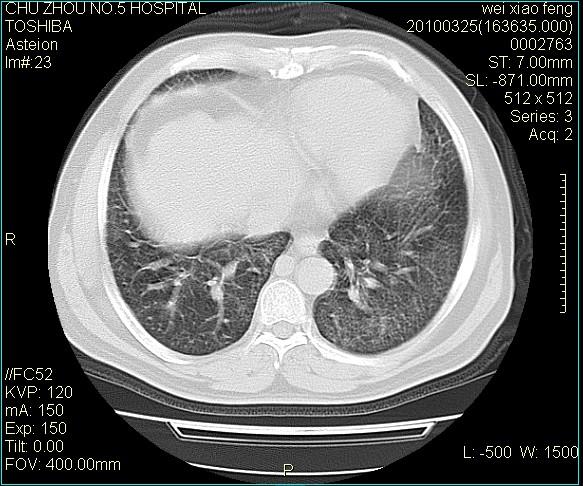

男,60岁,反复咳、痰、喘3月,加重3天。

双肺间质性改变。

考虑双肺血型潘散肺结核/

间质性肺炎伴间质纤维化!不排除伴有职业病!

急性血型潘散肺结核。

双肺间质纤维化,双肺血型潘散肺结核。

考虑间质性肺炎伴间质纤维化。

右肺中叶结节影为原发灶,考虑右肺中叶周围型肺癌并淋巴道转移